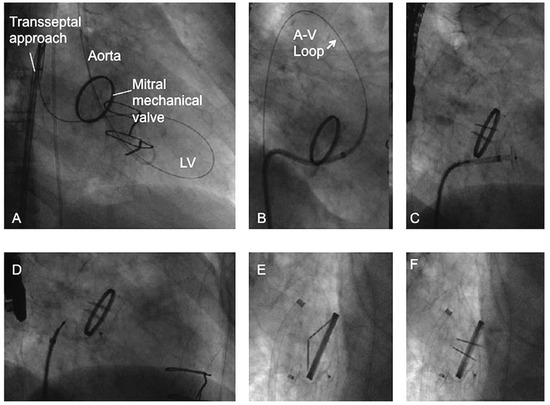

Transcatheter Prosthetic Paravalvular Leak Closure

by Stéphane Noble, Arsène Basmadjian and Réda Ibrahim

Cardiovasc. Med. 2012, 15(9), 245; https://doi.org/10.4414/cvm.2012.01695 - 26 Sep 2012

Cited by 9 | Viewed by 303

Paravalvular leak affects up to 27% of all prosthetic heart valves implanted by conventional surgery. Patients with paravalvular regurgitation can be asymptomatic or may present with symptoms of congestive heart failure and/or haemolytic anaemia. Assessment and quantification of these paravalvular leaks are difficult since transthoracic c olour flow Doppler images may be obscured by annular calcifications and prosthetic material. Surgical re-intervention is the conventional treatment of choice for severe cases but is associated with significant morbidity and mortality, and is not always successful because of underlying tissue fragility. Over the last decade, transcatheter treatment of paravalvular leaks has emerged as an attractive alternative to surgery for high-risk patients and is now favoured as the initial approach in some experienced centres. Transcatheter repair is technically feasible in 60 to 90% of cases according to different published series. Technical success is associated with clinical improvement in 50 to 90% of the cases. Full article

Show Figures

Figure 1